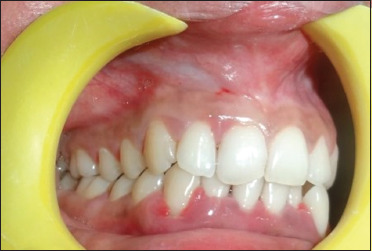

伴有口腔脱屑性病变的系统性红斑狼疮(SLE)是罕见的临床病例之一。牙周病和系统性红斑狼疮的发病机制多种多样,病理特征也各不相同。牙周炎和自身免疫性疾病的组织破坏机制具有相似的途径,越来越多的报道研究了这两种疾病之间的关联。本病例是一名 24 岁的女性患者,主诉牙间隙普遍增宽。同时,她还伴有脱发、虚弱、腿部水肿和关节痛。根据美国风湿病协会和欧洲皮肤病与性病学学会的标准,该患者在来看牙医的一年前被确认患有系统性红斑狼疮。她患有脱发、乏力、关节痛和腿部水肿。根据口腔、临床和影像学检查结果,她被诊断为侵袭性牙周炎病例。经过非手术牙周治疗,翻瓣,清创,用四环素进行根部调理后,在所有有角骨缺失的部位植入牛骨异种移植,然后用 4-0 丝线间断直接环形缝合技术缝合。每 6 周进行一次临床和影像学评估,以检查治疗的进展情况。6 个月和 8 年的随访结果显示,临床和影像学效果令人满意。根据本病例报告和以往的文献,我们推荐使用异种牙移植治疗侵袭性牙周炎患者。

Systemic lupus erythematosus (SLE) with oral desquamative lesions is one of the rare clinical entities. Periodontal disease and SLE display various mechanisms and possess a wide range of pathological characteristics. The tissue destruction mechanism of periodontitis and autoimmune diseases share similar pathways, and mounting reports studied the association between these two entities. The present case is of a 24-year-old female patient who complained of generalized widening of spaces in between the teeth. Along with it, She suffered from loss of hair, weakness, edema in the legs as well as arthralgia. The patient was identified to be suffering from SLE according to the American Rheumatism Association and European Academy of Dermatology and Venereology criteria 1 year before she reported to the dentist. She suffered from hair loss, weakness, arthralgia as well as edema in the legs. Based on the oral, clinical, and radiographic findings, she was diagnosed with aggressive periodontitis case. After nonsurgical periodontal treatment, the flap was reflected, debridement was done, after root conditioning with tetracycline, bovine osseous xenograft was placed in all the sites where ever there is angular bone loss, later sutured with interrupted direct loop suturing technique with 4-0 silk suture. Clinical and radiographic evaluation was done every 6 weeks to check the progress of the treatment. 6 months and 8-year follow-up revealed satisfactory clinical and radiographic outcomes. Based on the present case report and the previous literature, we recommend the use of xenograft in treating aggressive periodontitis patients.